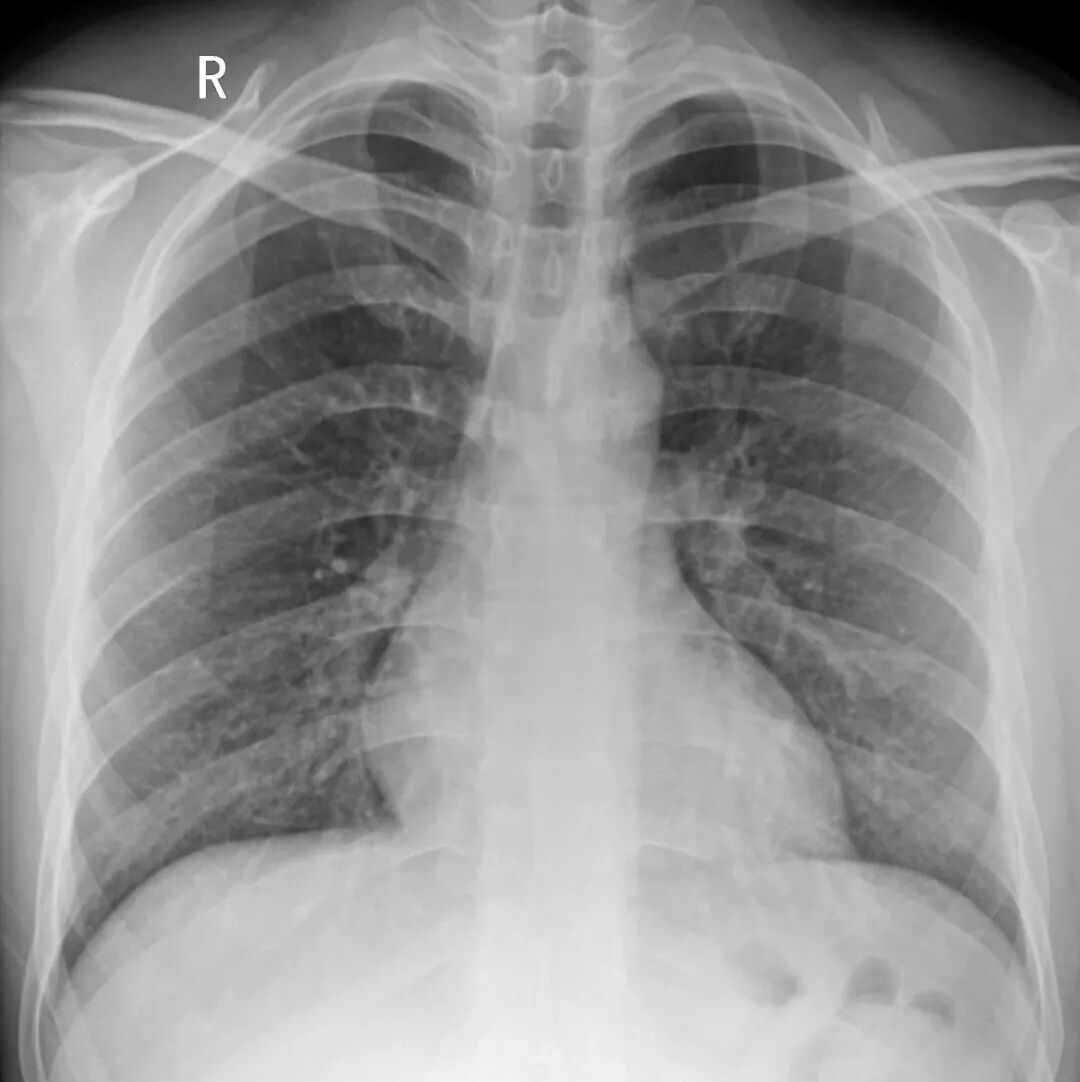

胸透和胸片主要用于检查诊断肺部疾病、心脏的大小、肋骨、胸膜、胸壁纵隔、支气管。为减少X线的损害,患者做检查不宜过多。

胸片DR和胸透还是有很大的区别的,当然它们都是检查胸部,也就是看肺这一块的。但是它们的区别还是比较大的,首先第一点它的辐射剂量有很大的差别,胸片DR,它的辐射剂量是非常的小,而胸透相对来说就要大一些了,主要是跟它辐射的时间有关系。

做胸片DR检查的话,它辐射的时间是非常短的,一般也就是零点零几秒的时间,非常的短,而胸透检查它这个辐射时间相对来说就要长一些了,一般是需要十秒钟的时间。当然如果发现有可疑的病灶,可能需要看的时间要更长一些了。正因为是这样,所以现在很多医院已经基本上取消了胸透检查了,都是用胸片来进行替代。

胸片的话一般是可以照出一张片子来,而胸透只是医生通过目视,通过眼睛来看,看完之后得出一个纸质报告,是没有这种片子的。

胸部 肺、胸膜及纵膈各种肿瘤、肺结核、肺炎、支气管扩张、肺脓肿、囊肿、肺不张、气胸、骨折等;对于显示肺部病变有非常满意的效果,对肺部创伤、感染性病变、肿瘤等均匀有很高的诊断价值。对于纵隔内的肿物、淋巴结以及胸膜病变等的显示非常清晰也令人满意,可以显示肺内团块与纵隔关系等。

最常用X光片、CT大致了解选X光片,细致分析选CT肺的检查一般不选核磁

胸部